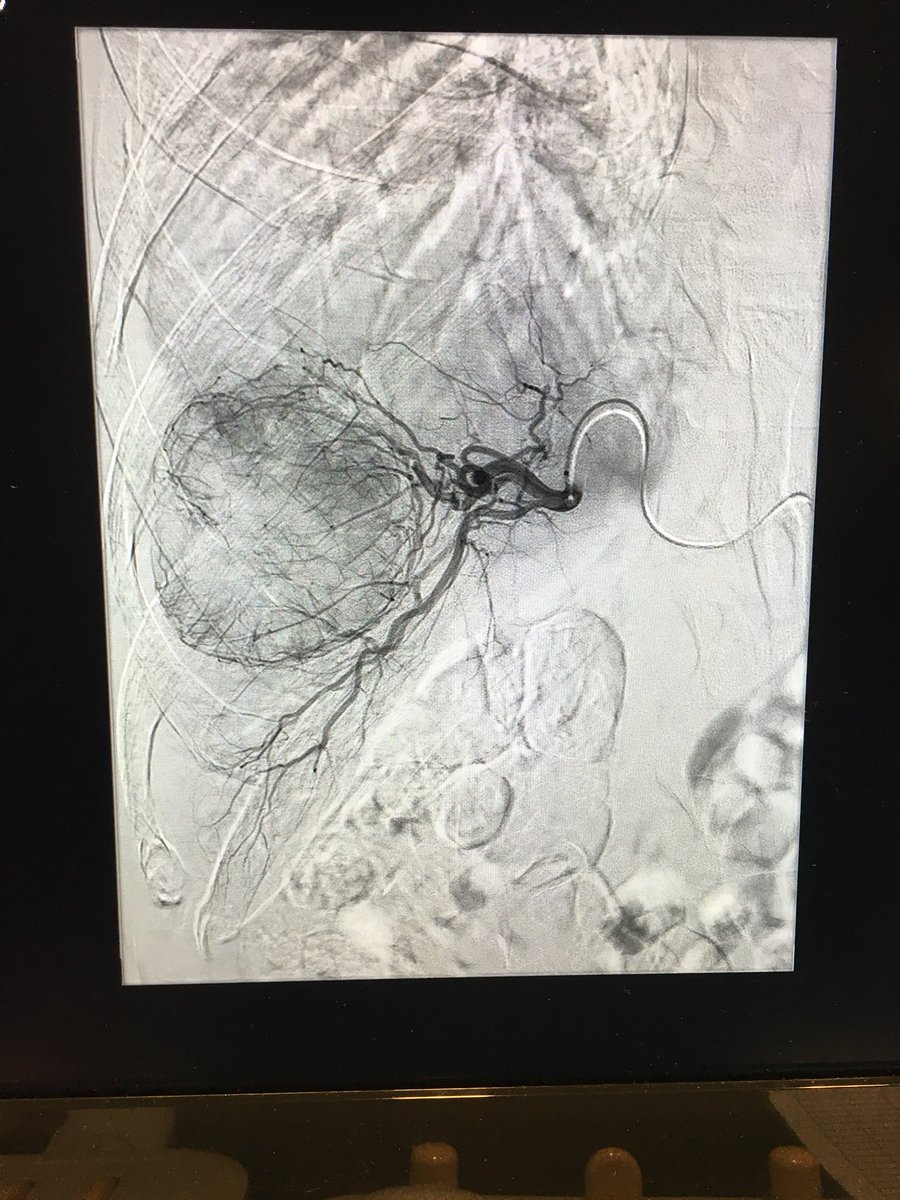

#IO meets #PAD | #iRad can treat cancer & vascular disease Pt w liver cancer, treated with #embolization 3 years ago. On clinic follow ups, patient complained of progressive claudication and recently developed ulcer at 3rd-4th toes. No problem! @rkryu Kumar Madassery Alexandria CVIR

Outpatient, same day discharge following #embolization via pinhole in the wrist #RadialFirst - large 7cm #renalAML #angiomyolipoma in @tsalliance kid. #IRad #twittIR University Hospitals UH Rainbow Babies UHNewsroom